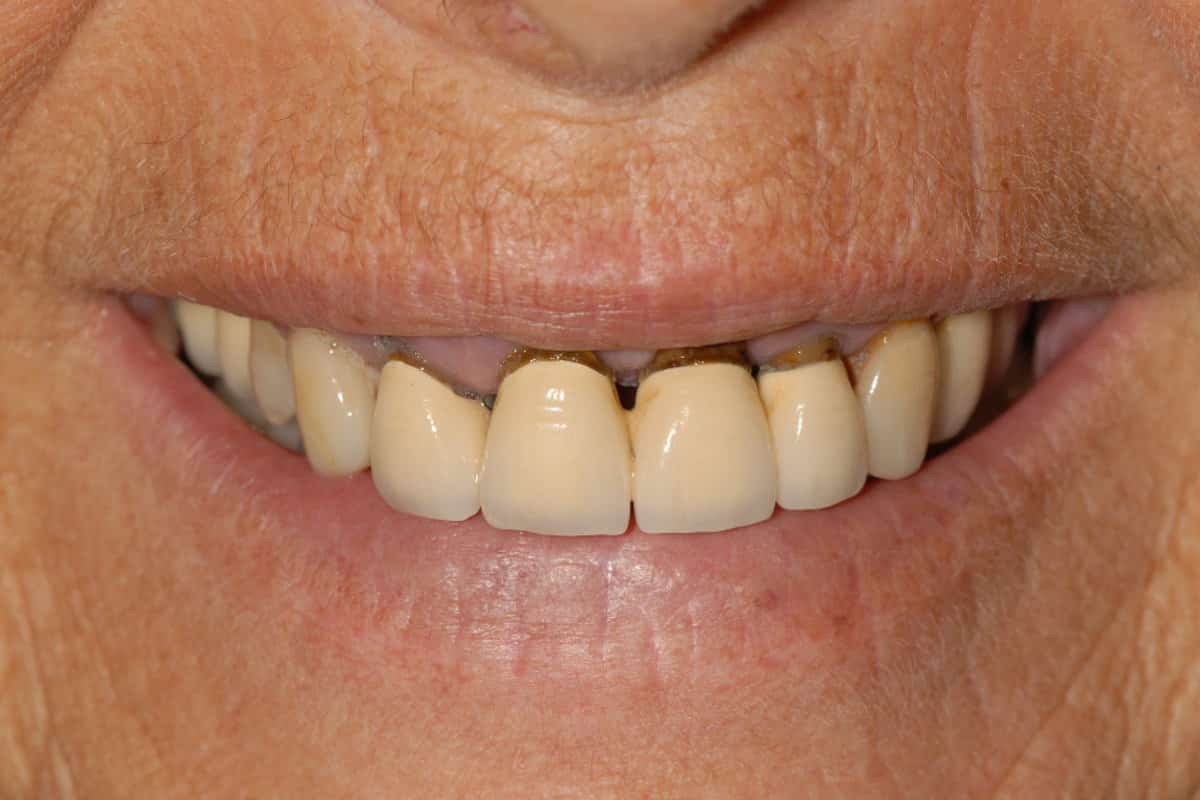

Caso clinico di parodontite grave: la situazione iniziale dell’arcata superiore

Nel giro di 24 ore dall’intervento alla paziente è stato consegnata una riabilitazione provvisoria fissa avvitata sugli impianti con l’emergenza dei denti dalle gengive naturali. Questo è uno degli aspetti fondamentali che contraddistingue e differenzia da protocolli tipo All-on-Four il concetto dell’Implantologia OnlyOne®.

La riabilitazione provvisoria in entrambe le arcate dopo Implantologia OnlyOne® a 24 ore dall’ultimo intervento